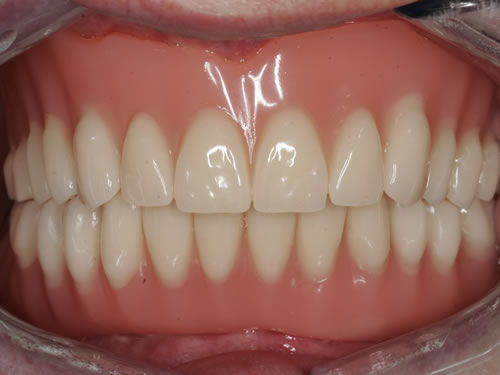

Eine besondere Herausforderung ist die Oberkieferfrontzahnregion. Der Wunsch nach einem perfekten Resultat ist geradezu selbstverständlich. Jeder möchte große, weiße Zähne und ein gesundes, reizloses Zahnfleisch besitzen (Abb. 3.30).

Abb. 3.30: Perfektes Resultat einer Versorgung.